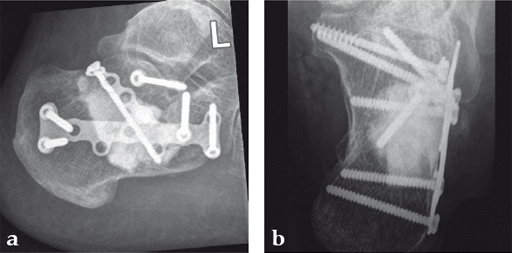

Case 2: A 38-year-old man sustained a lateral tibia plateau fracture (Müller AO Classification 41-B.3/Schatzker type II).

(Case provided by Michiel Verhofstad, Tilburg, The Netherlands)

After opening the lateral wedge, the osteochondral fragment was reduced and maintained with two K-wires. A gap beneath this fragment was left. Subsequently, a 3.2 mm hole was drilled in the lateral wedge using an inside-out technique. Then the lateral fragment was reduced. A 3-hole buttress plate, followed by two subchondral compression screws were used for final fracture fixation. Finally, Norian drillable was injected in the gap through the predrilled hole. Weight bearing was started after 6 weeks. At 6 months the fracture had healed anatomically and the patient was complaint-free.